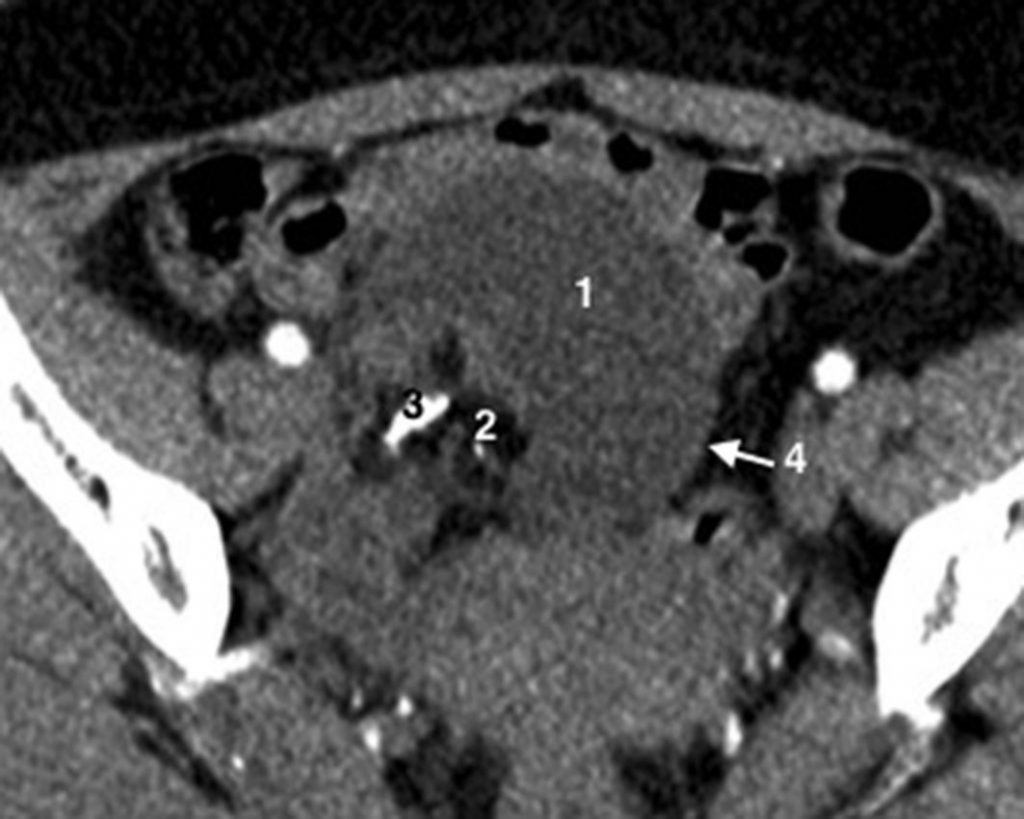

Fig. 20.5 Coupe axiale de scanner pelvien sans injection centrée sur un kyste ovarien droit mixte (liquidien et solide), même patiente que la figure 25.4.

1. Portion liquidienne. 2. Portion hypodense graisseuse. 3. Calcification. 4. Paroi du kyste.

Source : CERF, CNEBMN, 2022.